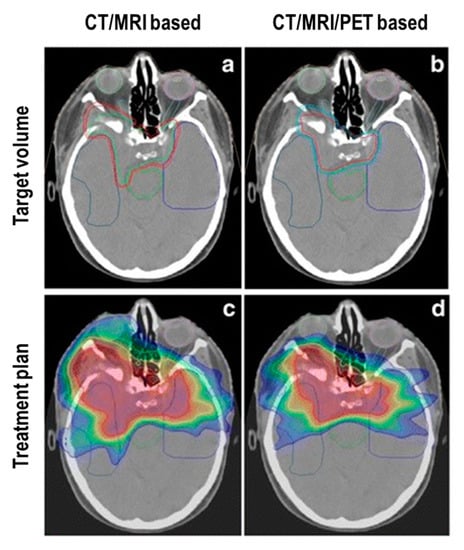

- Milker-Zabel, S.; Zabel-du Bois, A.; Henze, M.; Huber, P.; Schulz-Ertner, D.; Hoess, A.; Haberkorn, U.; Debus, J. Improved target volume definition for fractionated stereotactic radiotherapy in patients with intracranial meningiomas by correlation of CT, MRI, and [68Ga]-DOTATOC-PET. Int J. Radiat. Oncol. Biol. Phys. 2006, 65, 222–227. [Google Scholar] [CrossRef]

- Gehler, B.; Paulsen, F.; Oksüz, M.O.; Hauser, T.K.; Eschmann, S.M.; Bares, R.; Pfannenberg, C.; Bamberg, M.; Bartenstein, P.; Belka, C.; et al. [68Ga]-DOTATOC-PET/CT for meningioma IMRT treatment planning. Radiat. Oncol. 2009, 4, 56. [Google Scholar] [CrossRef]

- Nyuyki, F.; Plotkin, M.; Graf, R.; Michel, R.; Steffen, I.; Denecke, T.; Geworski, L.; Fahdt, D.; Brenner, W.; Wurm, R. Potential impact of 68Ga-DOTATOC PET/CT on stereotactic radiotherapy planning of meningiomas. Eur. J. Nucl. Med. Mol. Imaging 2010, 37, 310–318. [Google Scholar] [CrossRef]

- Graf, R.; Nyuyki, F.; Steffen, I.G.; Michel, R.; Fahdt, D.; Wust, P.; Brenner, W.; Budach, V.; Wurm, R.; Plotkin, M. Contribution of 68Ga-DOTATOC PET/CT to target volume delineation of skull base meningiomas treated with stereotactic radiation therapy. Int J. Radiat. Oncol. Biol. Phys. 2013, 85, 68–73. [Google Scholar] [CrossRef] [PubMed]

- Combs, S.E.; Welzel, T.; Habermehl, D.; Rieken, S.; Dittmar, J.O.; Kessel, K.; Jäkel, O.; Haberkorn, U.; Debus, J. Prospective evaluation of early treatment outcome in patients with meningiomas treated with particle therapy based on target volume definition with MRI and 68Ga-DOTATOC-PET. Acta Oncol. 2013, 52, 514–520. [Google Scholar] [CrossRef] [PubMed]

- Madani, I.; Lomax, A.J.; Albertini, F.; Trnková, P.; Weber, D.C. Dose-painting intensity-modulated proton therapy for intermediate- and high-risk meningioma. Radiat. Oncol. 2015, 10, 72. [Google Scholar] [CrossRef] [PubMed]

- Stade, F.; Dittmar, J.O.; Jäkel, O.; Kratochwil, C.; Haberkorn, U.; Debus, J.; Combs, S.E. Influence of 68Ga-DOTATOC on sparing of normal tissue for radiation therapy of skull base meningioma: Differential impact of photon and proton radiotherapy. Radiat. Oncol. 2018, 13, 58. [Google Scholar] [CrossRef] [PubMed]

- Maclean, J.; Fersht, N.; Sullivan, K.; Kayani, I.; Bomanji, J.; Dickson, J.; O’Meara, C.; Short, S. Simultaneous 68Ga DOTATATE Positron Emission Tomography/Magnetic Resonance Imaging in Meningioma Target Contouring: Feasibility and Impact Upon Interobserver Variability Versus Positron Emission Tomography/Computed Tomography and Computed Tomography/Magnetic Resonance Imaging. Clin. Oncol. (R. Coll. Radiol.) 2017, 29, 448–458. [Google Scholar] [PubMed]

- Acker, G.; Kluge, A.; Lukas, M.; Conti, A.; Pasemann, D.; Meinert, F.; Anh Nguyen, P.T.; Jelgersma, C.; Loebel, F.; Budach, V.; et al. Impact of 68Ga-DOTATOC PET/MRI on robotic radiosurgery treatment planning in meningioma patients: First experiences in a single institution. Neurosurg. Focus 2019, 46, E9. [Google Scholar] [CrossRef]